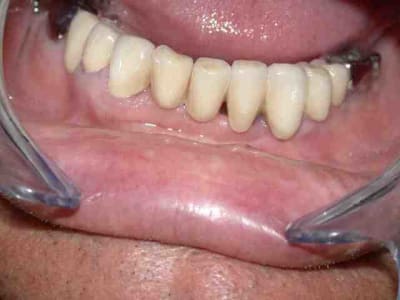

dépose des anciennes couronnes réalisation d'un bridge provisoire : la je peux vous dire que le patient est plus qu'heureux

couronnes unitaires sur 42 41 (41 mal située position un peu trop lingual : la vue linguale de la photo montre notre solution prothétique pour l'axe)

pano et photos a suivre les photos sont pas tops car vieil apparei et je vous le rappelle (reflex nauseeux,faut pas aller chercher trop loin quand même , mais vous verrez à la fin on met des écarteurs photos si si...)